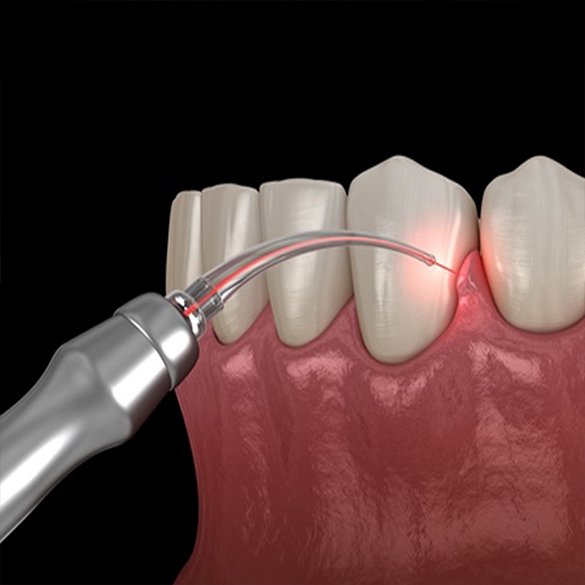

Our services and expertise

Routine & emergency services

Dental treatment